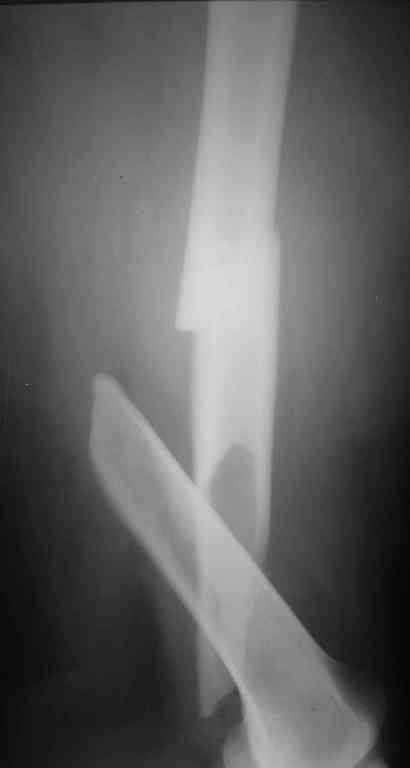

К сожалению никакой информации кроме рентгенограммы

одного из бедер, и то в одной проекции не представлено. Но и исходя из представленного снимка я бы предпочёл длинную гамму(производитель в принципе значения не имеет, если это не подпольная организация).

По представленному снимку выполнял бы антеградное введение стержня, длинна дистального отломка позволяет. Только блокирование более чем в одной плоскости.

Современная генерация бедренных гвоздей ChM позволяет "перекрыть" все бедро. Почему "правый гвоздь на левое бедро"?

Я бы поставил слева любой проксимальный гвоздь. Подойдет и стандартный СhM в "реконструктивном" варианте. А справа - хоть антеградно, хоть ретроградно - кому что нравится. Я бы колено сверлить не стал. Ввел бы в дистальный отломок 3-4 винта обязательно в 2-х плоскостях.